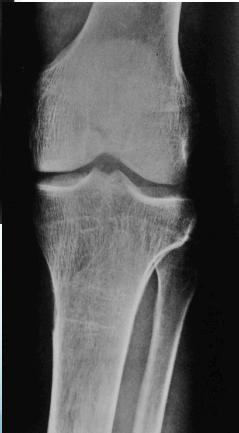

- âBrown tumorsâ: (coagulated blood-filled cystic spaces)

Lytic lesions caused by hyperparathyroidism are called Brown tumors. The term âBrown tumorâ is a misnomer because it is not a true neoplasm.

- Sub-periosteal resorption: middle phalanges, tibial shaft